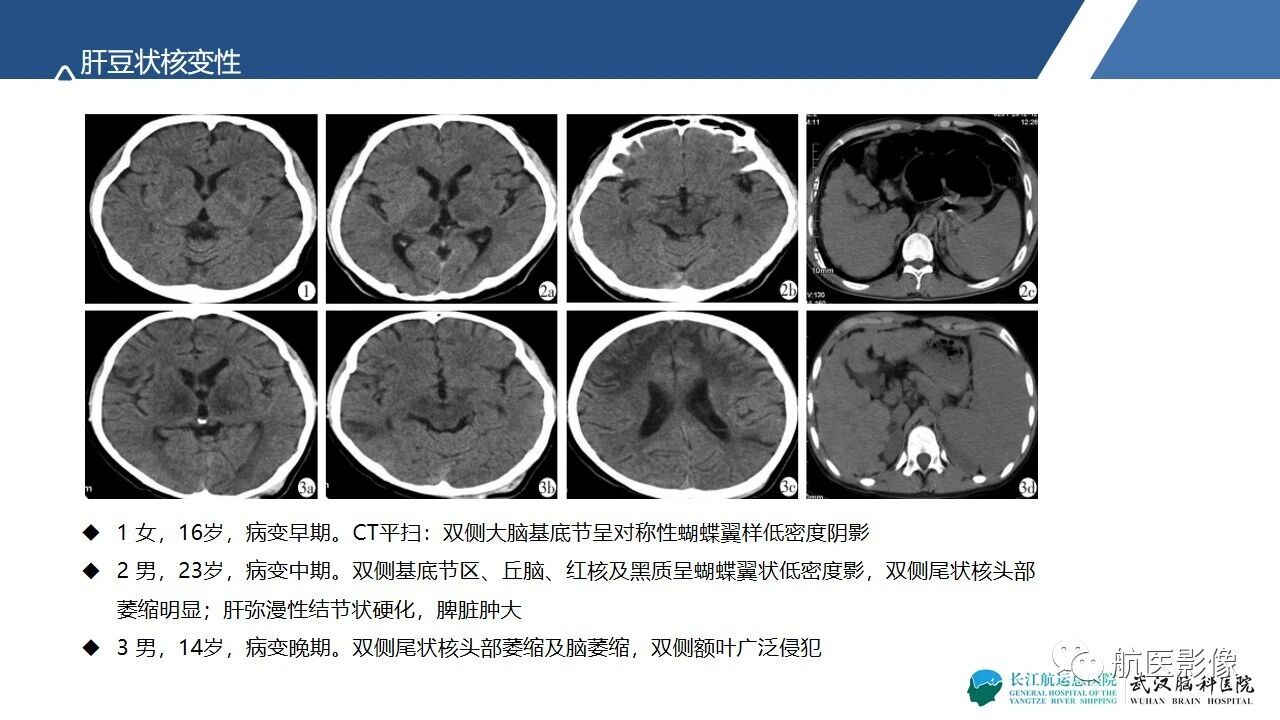

基底节区、丘脑对称性病变影像表现